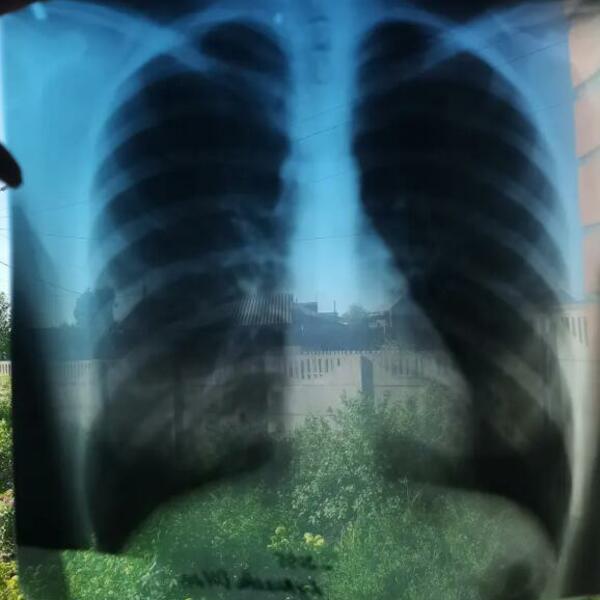

Međutim, lekari Olesji nisu mogli da daju dijagnoze sve dok nisu ustanovili da su njeni organi potpuno na pogrešnom mestu.

Ova 27-godišnjakinja pati od retkod stanja abnormalnosti organizma koje karakteriše potpuno suprotan raspored organa, sve što se u normalnom organizmu nalazi normalno kod nje je obrnuto.

A otkriva se uz pomoć rengenskih snimaka, MRI ili ultrazvuka.

Ona je imala samo 14 godina kada su joj otkrili da joj se srce nalazi na desnoj strani tela. Zatim četiri godine kasnije, sa 18 godina rečeno joj je da joj se jetra nalazi takođe na desnoj strani tela. A zbog upale pluća koja ju je zadesila 2019. godine lekari su joj otkrili da su pluća locirali uz pomoć reflekta ogledala.